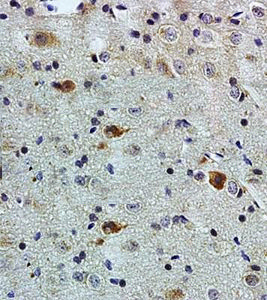

Anti-PACAP antibody GTX37576 from GeneTex | Biocompare.com。Anti-Desmin antibody [Y66] - Low endotoxin, Azide free。Anti-Desmin antibody [Y66] - Low endotoxin, Azide free。7820 INHEEL SLIPON | MUUM。。x1 red strawberryx1 pink strawberryx1 pink tigerx1 seal x1 pig

![Anti-Desmin antibody [Y66] - Low endotoxin, Azide free Anti-Desmin antibody [Y66] - Low endotoxin, Azide free](https://content.abcam.com/products/images/desmin-antibody-y66-low-endotoxin-azide-free-ab216616--immunohistochemistry-formalin-pfa-fixed-paraffin-embedded-sections-img128436.jpg)

![Anti-Desmin antibody [Y66] - Low endotoxin, Azide free Anti-Desmin antibody [Y66] - Low endotoxin, Azide free](https://content.abcam.com/products/images/desmin-antibody-y66-low-endotoxin-azide-free-ab216616--immunohistochemistry-formalin-pfa-fixed-paraffin-embedded-sections-img135003.jpg)